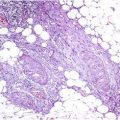

Fig. 37.1

Kaposiform hemangioendothelioma. Irregular tumor nodules growing in an infiltrative fashion and evoking a dense hyaline stromal response (Courtesy of H.Kutzner, Friedrichshafen)